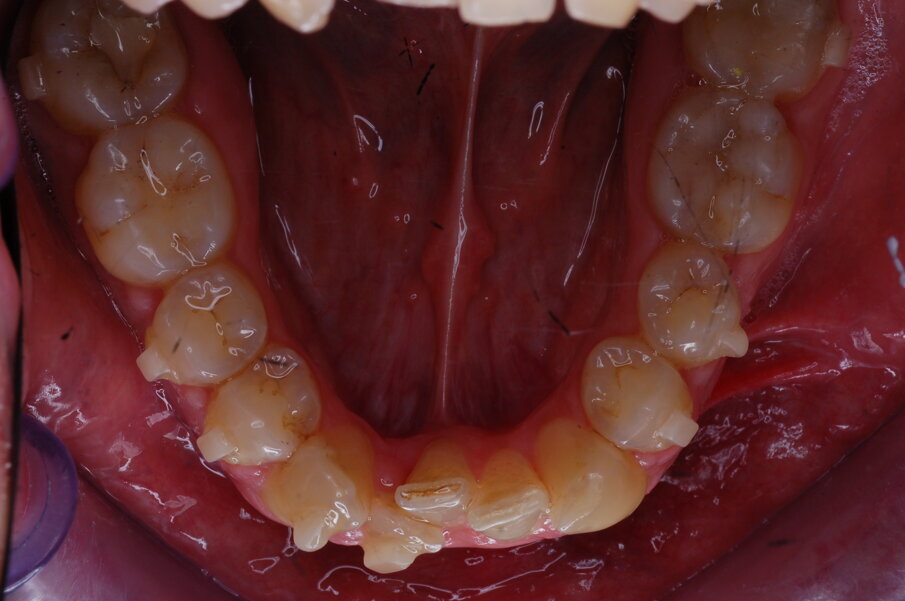

Diagnosi ed eziologia Un uomo sano di 39 anni si è presentato nel nostro studio ortodontico lamentando un aspetto dentale poco attraente e la paura della chirurgia ortognatica proposta da un altro ortodontista. Clinicamente, il profilo del paziente era rettilineo e la vista frontale non mostrava alcuna asimmetria facciale. L’esame funzionale non ha rivelato alcuna deviazione mandibolare o riduzione dei movimenti. Il paziente non aveva dolori articolari e non sono stati rilevati rumori articolari. Era presente una lieve occlusione molare bilaterale di Classe II, un morso aperto e un grave affollamento in entrambe le arcate. L’affollamento era particolarmente grave nell’arcata mandibolare, sebbene mancasse l’incisivo centrale mandibolare destro. Gli incisivi mascellari erano di piccole dimensioni, suggerendo una discrepanza dell’indice di Bolton se fossero stati presenti tutti e quattro gli incisivi mandibolari. Erano inoltre presenti un morso incrociato nella regione dell’incisivo laterale superiore sinistro e una grave rotazione distale del secondo premolare mandibolare sinistro (Figg. 1-8).

Figg. 1-8_Fotografie facciali e intraorali pre-trattamento.